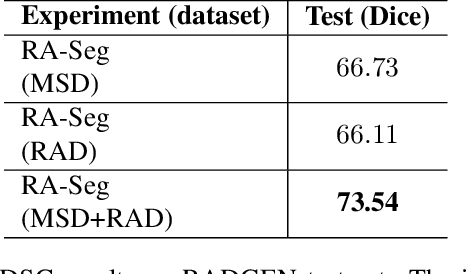

Lung cancer is a leading cause of death worldwide. Early-stage detection of lung cancer is essential for a more favorable prognosis. Radiogenomics is an emerging discipline that combines medical imaging and genomics features for modeling patient outcomes non-invasively. This study presents a radiogenomics pipeline that has: 1) a novel mixed architecture (RA-Seg) to segment lung cancer through attention and recurrent blocks; and 2) deep feature classifiers to distinguish Epidermal Growth Factor Receptor (EGFR) mutation status. We evaluate the proposed algorithm on multiple public datasets to assess its generalizability and robustness. We demonstrate how the proposed segmentation and classification methods outperform existing baseline and SOTA approaches (73.54 Dice and 93 F1 scores).